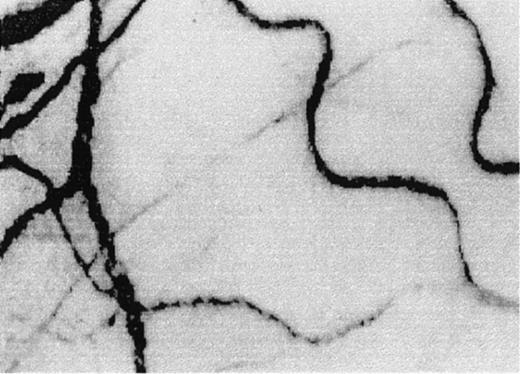

The microcirculation in the bulbar conjunctiva of the eye.

Optical magnification, × 4.5; onscreen magnification, × 125. A indicates arteriole; V, venule; H, hemosiderin deposit; S, blood sludging; BW, sacculated vessels (beaded or sausage-shaped); and BC, intermittent boxcar blood flow phenomenon. (A) A typical view of the conjunctival microcirculation of a healthy non-SCD subject to serve as reference (35 mm photograph). Note the even and orderly distribution of the normal-sized arterioles and venules and the normal presence of capillaries. (B) The steady-state conjunctival microcirculation of a patient with nonsevere SCD complications (hard copy of a frame-captured image). All the arterioles and venules in the field are wider in diameter than in non-SCD controls. The bulbar conjunctiva of this SCD patient is adequately vascularized; however, vessel distribution is disorganized and uneven, differing from the healthy non-SCD controls. In addition to blood sludging (S), the overall blood flow is sluggish and intermittent as indicated by the presence of the boxcar blood flow phenomenon (BC) in some vessels. The resolution and clarity of this frame-captured image is comparable to a 35 mm photograph (panel A). (C) The steady-state conjunctival microcirculation of another patient with nonsevere SCD complications (frame-captured image). All the vessels in this image are significantly (P < .01) wider in diameter than non-SCD control vessels, and vessel distribution is uneven. Note the unique absence of capillaries and the reduced presence of arterioles and venules in the upper left region of the figure, giving that location a blanched appearance. In addition, sacculated vessels (BW) (beaded or sausage-shaped vessel) and blood sludging (S) are present. (D) The steady-state microcirculation of a patient with severe SCD complications (frame-captured image). Hemosiderin deposits (H) are present, denoting previous extravasation of blood from damaged vessels. The venules are significantly (P < .01) wider in diameter than control vessels. In addition, blood sludging (S) and sacculated vessels (BW) are present.

Two frame-captured steady-state images of the conjunctival microcirculation showing additional microvascular abnormalities.

Optical magnification, × 4.5; onscreen magnification, × 125. (A) Inadequate vascularization (avascularity), two types of comma signs (CS1 and CS2), blood sludging (S), and the intermittent boxcar (sluggish) blood flow phenomenon (BC) are present. (B) Another view of comma signs (CS1), blood sludging (S), and the boxcar blood flow phenomenon (BC).